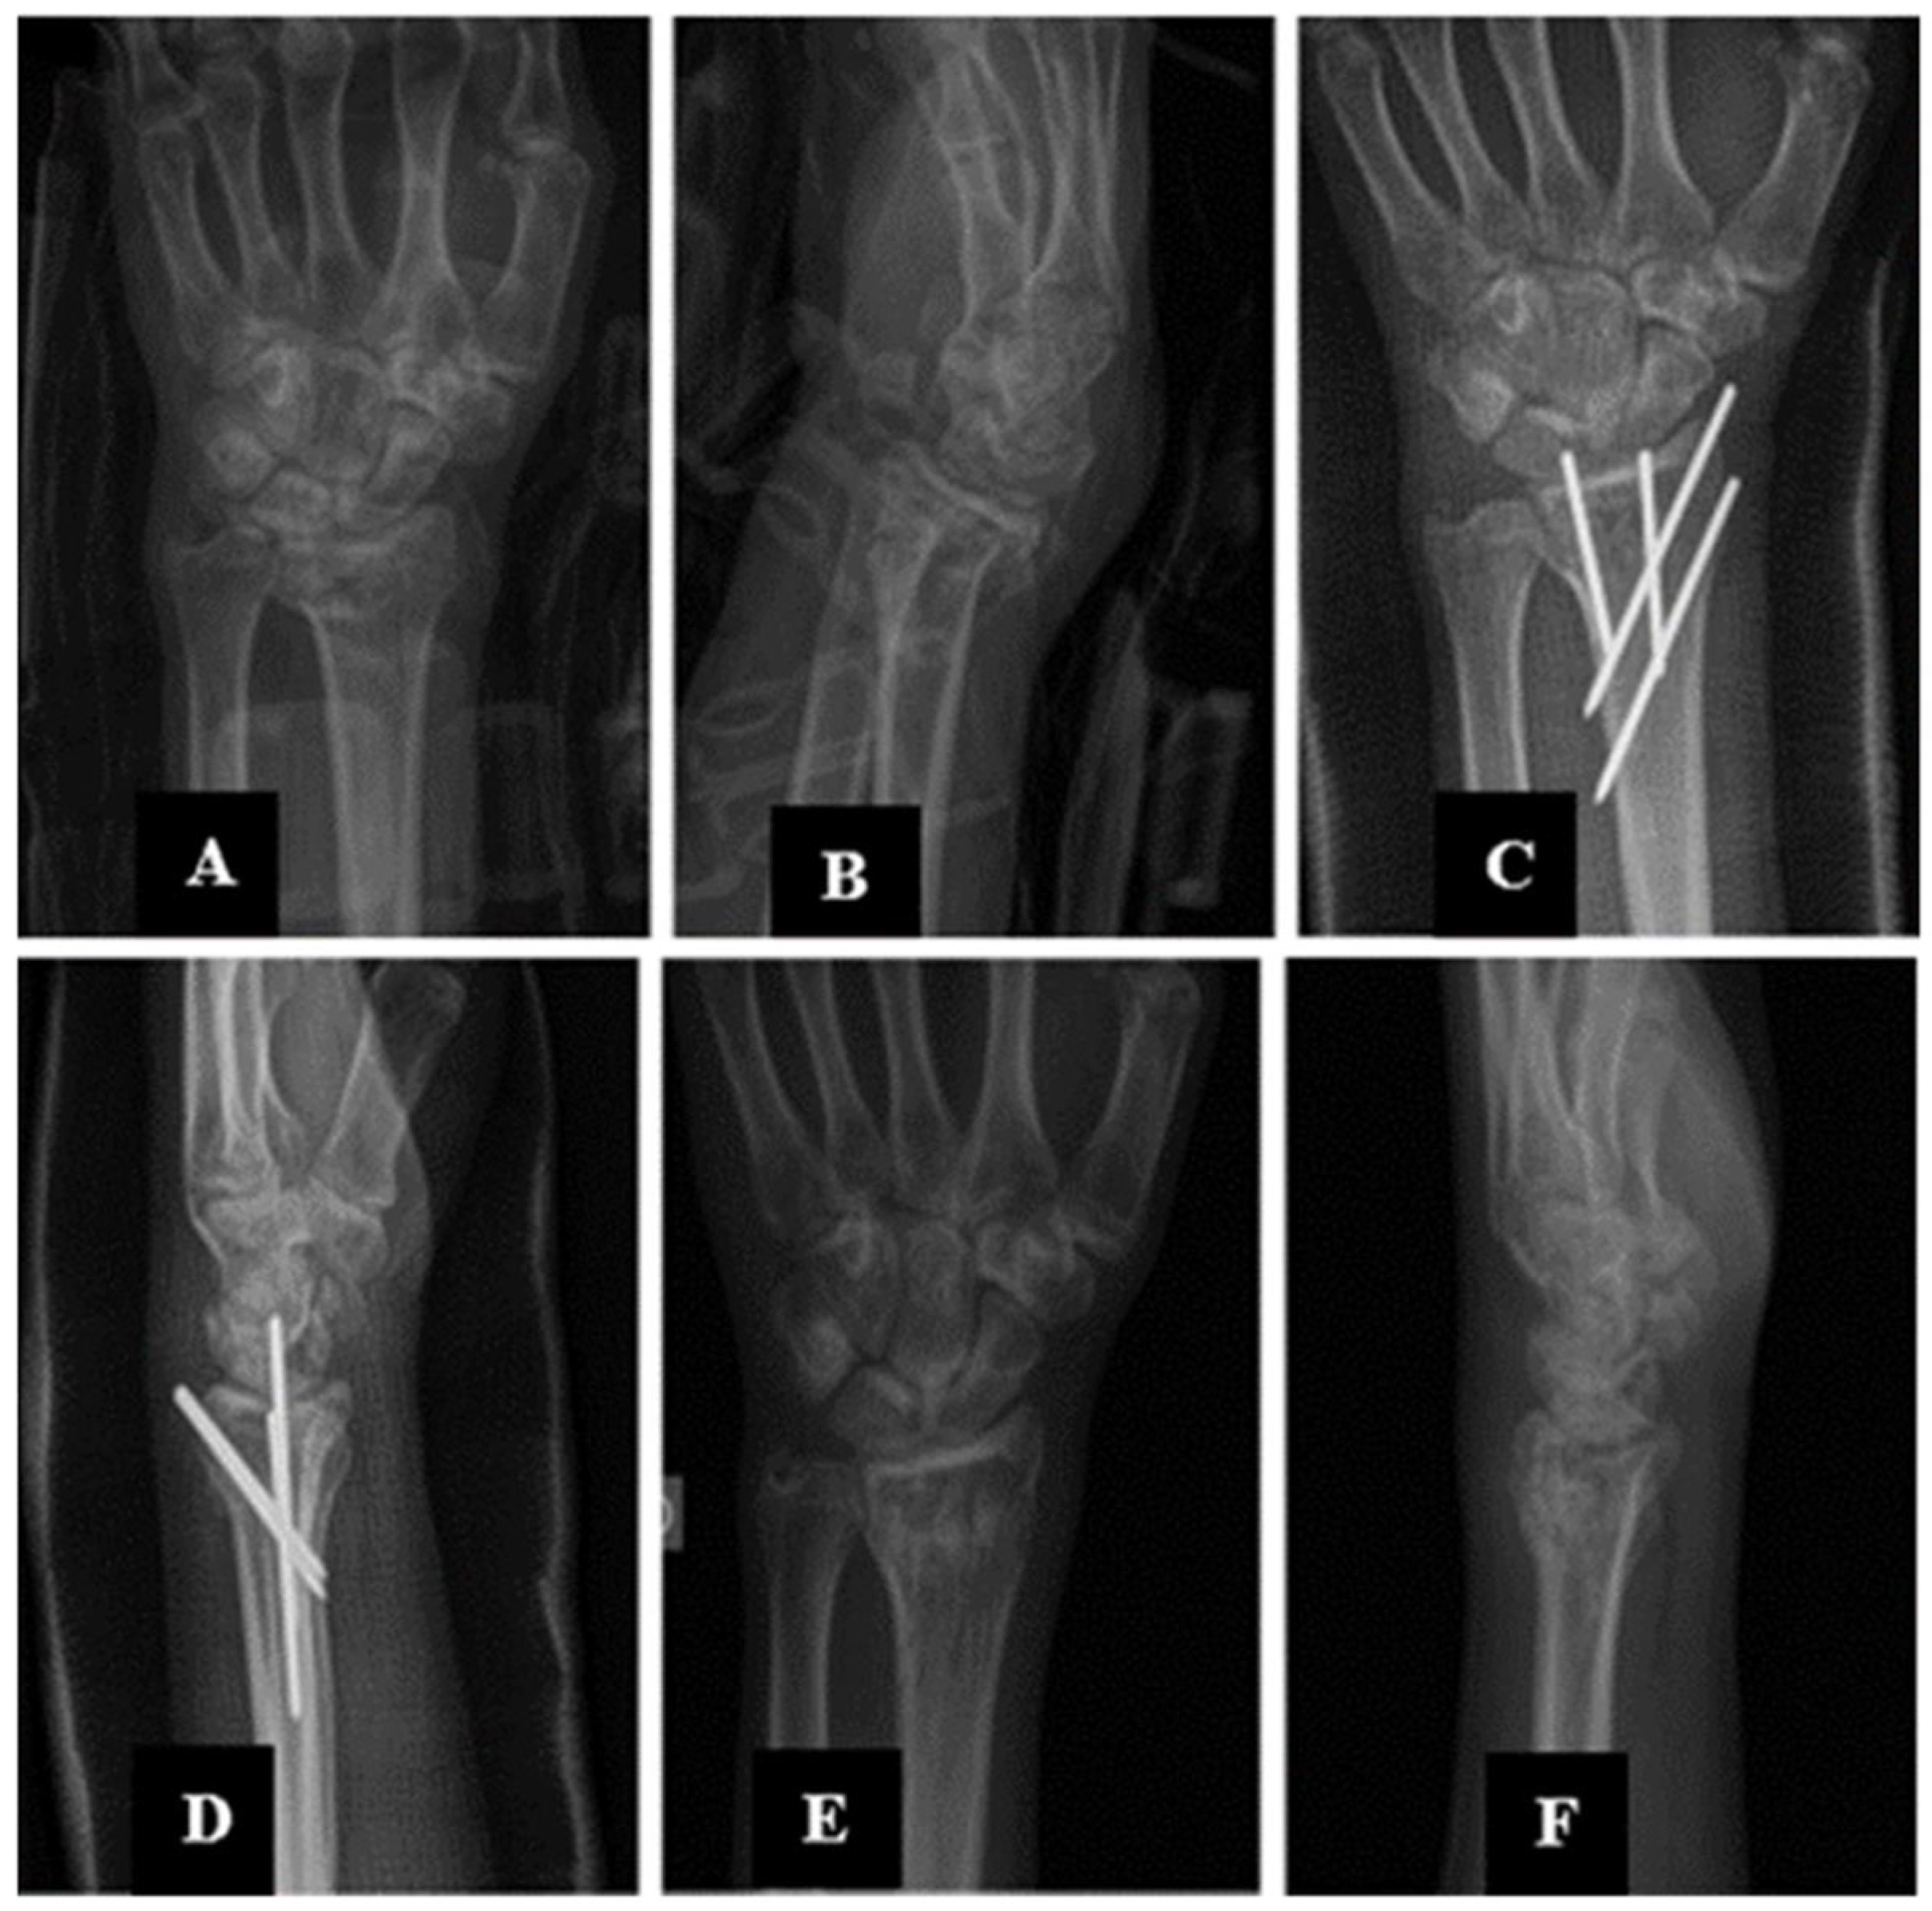

Surgical Treatment of Distal Radius Fractures Using Minimally Invasive Plate Osteosynthesis or Open Reduction and Internal Fixation: A Five-Year Comparative Follow-Up Study

2. Materials and Methods

2.3. Description of the Experimental Stage